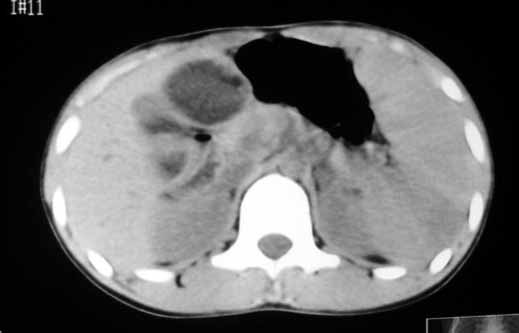

以下是引用zhangzhongshou在2007-5-22 21:04:00的发言:[br]1、脾肿大[br]2、脾脏低密度影,血管瘤?脾梗塞不能除外,建议增强扫描。

以下是引用dyqct在2007-5-22 20:45:00的发言:[br]巨脾,可疑梗塞,建议增强、查血象进一步检查

以下是引用liuyue在2007-5-23 7:57:00的发言:[br]腹主动脉周多个肿大淋巴结,脾大伴三角形低密度影,肠腔积气,考虑:1淋巴瘤2脾大伴梗塞3肠腔积气(肿大淋巴结压迫所致)